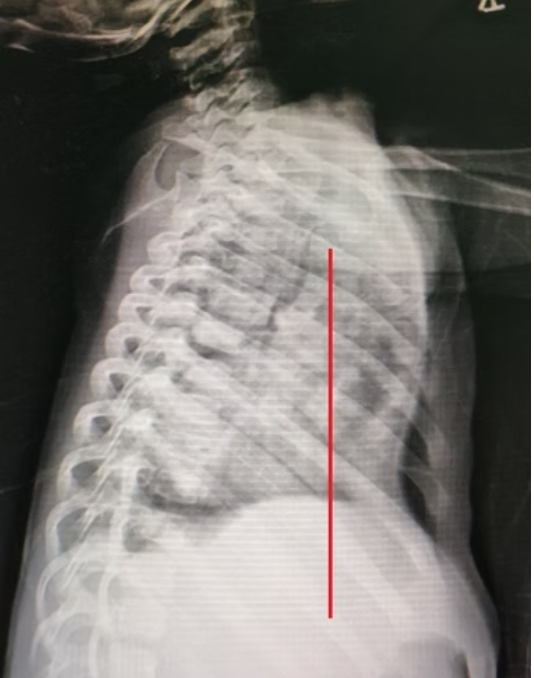

Pectus excavatum is a common congenital deformity that causes the sternum and adjacent ribs to sink inward, giving the chest a sunken appearance. In some people, the indentation is mild and only affects appearance, while in others, the indentation is deeper and more severe, potentially leading to breathing difficulties or pressure on the heart.

Doctors will determine the severity of the condition by evaluating the patient’s clinical presentation and physical signs, as well as imaging studies such as X-rays, chest CT scans, and electrocardiograms. Treatment plans depend on age, symptoms, and the type and severity of the deformity. Modern minimally invasive surgical techniques, such as the Wang procedure and the Wung procedure, can be used to repair the shape and function of the chest wall while minimizing damage.